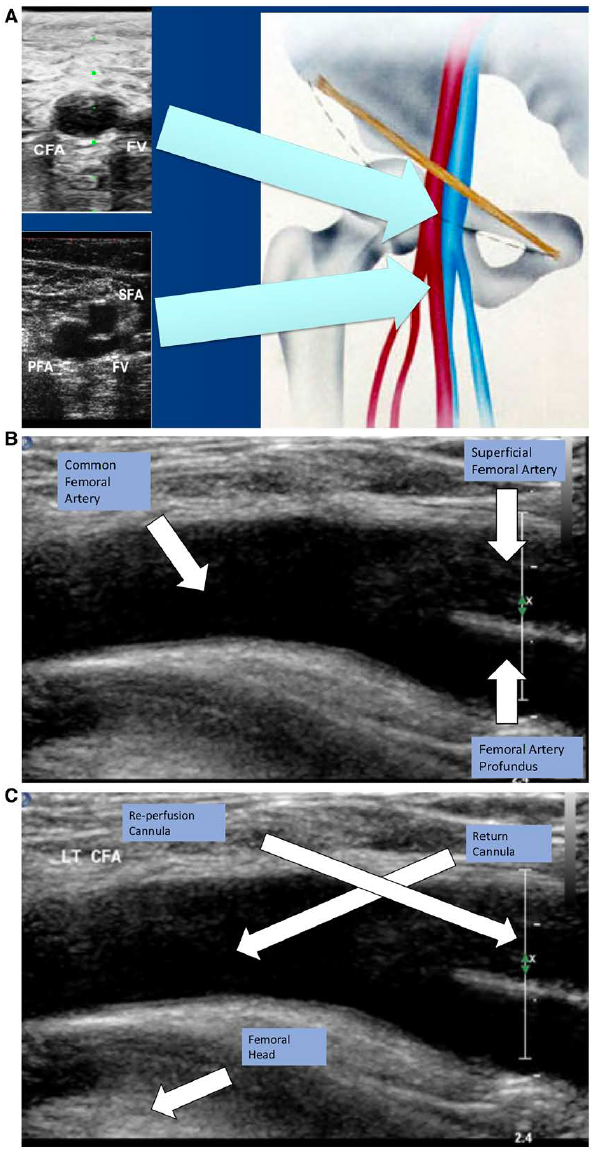

推荐使用可视化技术引导置管,尤其是血管超声作为首选。X线透视可用于特定场合,比如在导管室置管。血管超声应从短轴和长轴图像开始。我们推荐从短轴图像开始,识别股总动脉和静脉、股浅动脉和股深动脉(见图4A),然后旋转90o至长轴图像,使股总动脉及其分叉可视化(见图4B)。它可引导穿刺针从前方刺入血管,并且避免刺伤后壁。此外,使用股骨头作为标识可确保血管通路位于血管的可压缩部分,避免置入骨盆(见图4C)。类似技术也推荐应用于股总静脉置管。

图4: A:短轴血管超声显示CFA和CFV、SFA和PFA分叉、腹股沟韧带和股骨头的关系。注意股浅动脉下面的FV路径。B:当CFA分叉至股浅动脉和PFA时的纵向血管超声。C:股动脉的纵向血管超声显示与股骨头的关系,以及动脉回插管和远端灌注导管的进针位置(由Dr. Wallace Ngai提供,香港)。CFA:股总动脉; CFV:股静脉; FV:股静脉; PFA:股深动脉; SFA股浅动脉。